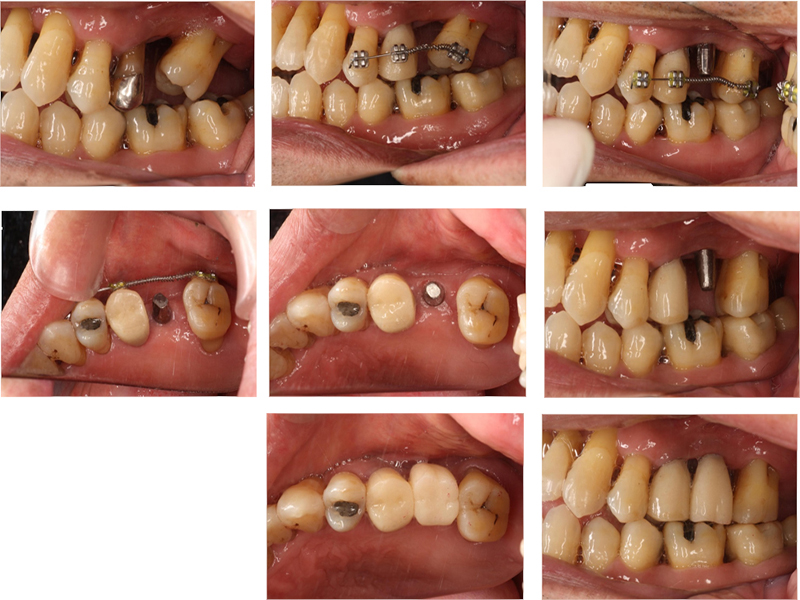

初診

治療中